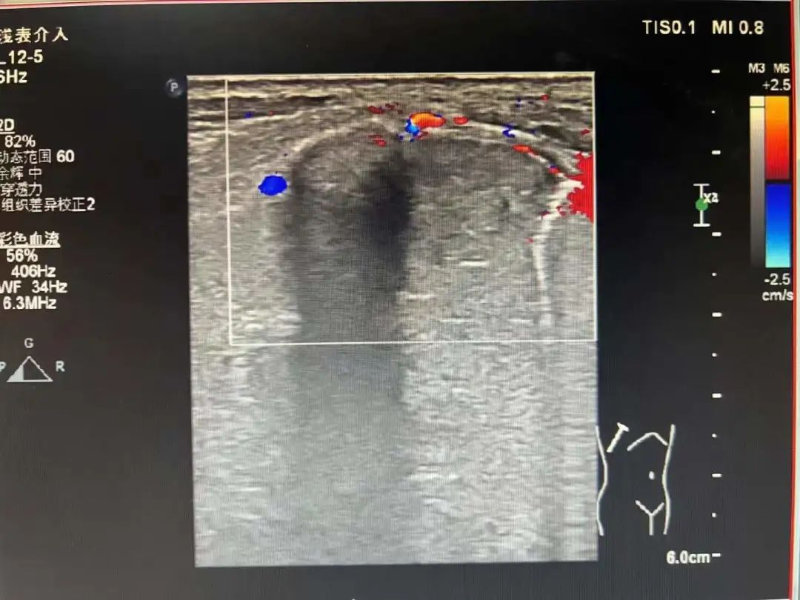

無獨有偶,3月16日,林伯伯(化名)四天前開始出現陣發性雙側胸痛,并伴有咳嗽、咳痰,遂到我院就診。門診檢查胸部增強CT顯示右肺上葉占位,疑是原發性支氣管肺癌,收治入院。

為進一步診斷病情,3月17日在陳勇輝超聲引導下,超聲醫學科蔣朝霞主任醫師為林伯伯進行肺腫瘤穿刺活檢。超聲引導下以右肺腫瘤最清楚處為目標,用穿刺針沿著引導線刺入,通過針尖穿越腫瘤觸發活檢槍進行活檢。穿刺后,林伯伯無不適。我院超聲醫學科成功完成穿刺活檢,為患者進行專科治療做“最強輔助”,充分體現了我院超聲醫學科能力水平的綜合提升,讓患者能就近就醫、就近診斷,為患者減輕看病就醫經濟負擔和解決奔波勞碌的問題。